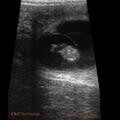

Pregnancy scanning is performed during milking for rotary and in between milkings for herringbone sheds. We send two scanners out so that we can keep up with milking speed for rotaries and finish herringbone sheds quickly so the cows can get back onto grass quickly. We offer the use of our vet technician team for recording results straight into Infovet/MINDA for efficient data management and results reporting within 24 hours. We can age pregnancies accurately from 35 days to 90 days.